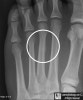

발의 AP view, lateral view, oblique X-ray 촬영을 실시합니다.

손상 후 2~3주까지는 X-ray에 안 보일 수 있으므로 시간이 지나 재촬영을 해야 합니다.

X-ray : 중족골 피로골절(Metatarsal stress fracture)